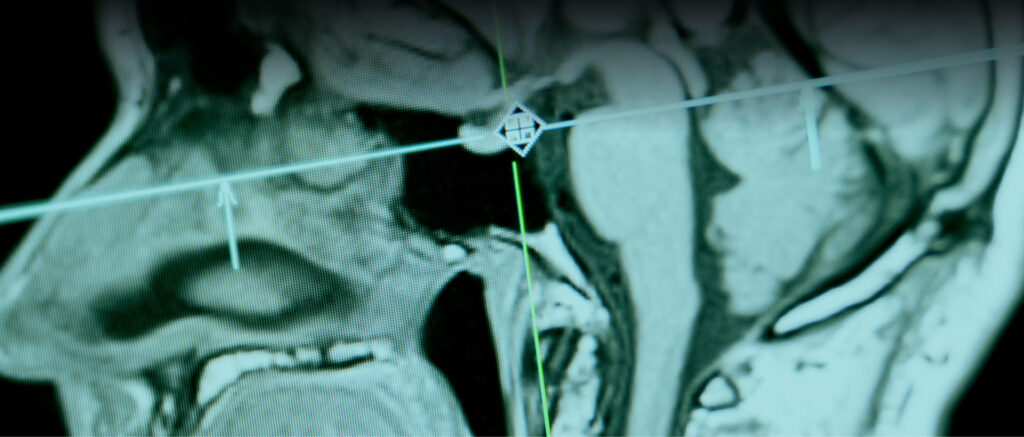

A neuro-oncologia é a área da medicina dedicada ao diagnóstico e tratamento de tumores que afetam o cérebro e a medula espinhal. Esses tumores podem ser benignos ou malignos e, dependendo de sua localização, podem comprometer funções neurológicas essenciais, como a fala, a coordenação motora e a memória. O diagnóstico geralmente envolve exames de imagem avançados, como ressonância magnética e PET Scan, permitindo uma avaliação detalhada da lesão.O tratamento da neuro-oncologia é multidisciplinar e pode incluir cirurgia, radioterapia, quimioterapia e terapias-alvo, escolhidas conforme o tipo e estágio do tumor. O objetivo é não apenas eliminar ou controlar o crescimento da lesão, mas também preservar a qualidade de vida do paciente, minimizando impactos cognitivos e motores. Os avanços na medicina vêm possibilitando abordagens cada vez mais precisas e eficazes, aumentando as chances de recuperação e melhora dos sintomas.

Auxiliam no diagnóstico e monitoramento dos tumores com exames de imagem.